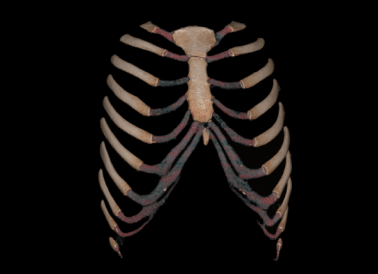

原理先容:肋软骨由于其因素在x线平片及通例CT上难以显示。多层螺旋CT有着众多优点,如笼罩规模大、可提供多层扫描数据的信息、密度区分率高、图像后处置惩罚功效强盛

临床用途:整形外科医生使用肋软骨作为支架重塑鼻已成为普遍需求,而在取肋软骨之前,要先确定肋软骨是否钙化。CT“肋软骨三维重修”可确定软骨是否钙化,并选择理想的肋软骨